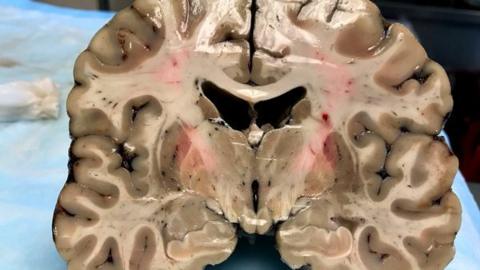

Hernandez, who was diagnosed as being in stage 3 out of 4 of the disease, had suffered substantial damage to key parts of his brain, which is thought to have heavily impacted his behaviour and. Explore shocking findings from aaron hernandez's brain study, revealing severe cte and its potential impact on his tragic life and actions. The neuroscientist who analyzed aaron hernandez's brain has confirmed that he suffered the worst case ever seen in.